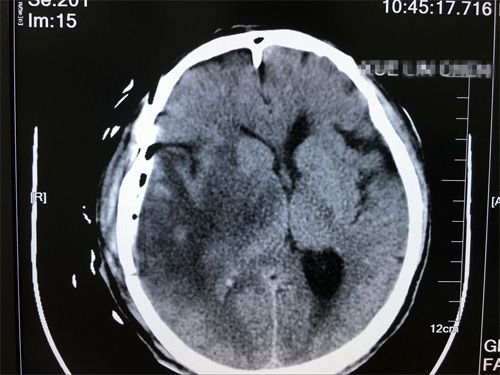

术后影像:未见肿瘤残余,未见异常明显病灶

在手术过程中,沈建康教授在显微镜下利用工具非常娴熟地进行探测、剥离、止血、冲洗,不放过任何一个可能隐藏肿瘤的部位,用镊子和剪刀将肿瘤物夹取,剪取... 最后,护士将器皿中的肿瘤物放入标本瓶,送去进行病理化验。手术后,薛老汉被送到重症监护室密切观察。他意识清醒,表达无误,四肢活动无障碍。其实在胶质瘤切除手术过程中,有两个难点,一个是肿瘤边界判断,尽可能保证全切,另一个是神经功能保留,让患者在术后有较高的生活质量,这两点,沈教授都做到了。

手术后第3天,陈老汉平安转到普通病房,术后第5天,引流管顺利拔除,在家人的照顾下,恢复越来越好。薛老汉的女儿说:“真的非常感谢沈教授,以很快的速度帮我们解除了痛苦,现在父亲终于不要再受脑瘤折磨了。看着他身体一点点好转,我们做子女的遗憾也少一点”。除了感谢沈教授,薛老汉的女儿还对医院的服务赞不绝口,她说:“父亲在这里住院,一个病房的患者和家属相处都非常融洽,医生每天查房,很有耐心,护士姑娘们也非常温柔,脾气很好。马上就要出院了,真的十分感谢各位病友和医护人员的照顾”。